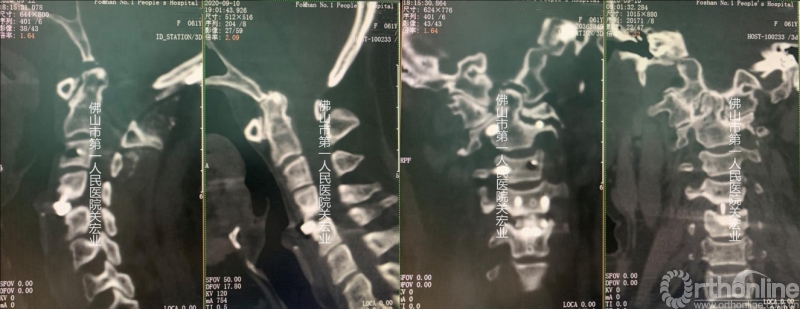

术后分析:

影像学术前、术后对比

A:术后颈后、枕部向头顶的放射痛明显缓解。左上肢肌力提高一级,双侧下肢本体感觉改善。术前寰枢椎旋转脱位、下颌偏歪、齿状突上移、脊髓向右侧偏移的情况,术后影像学可见均有明显改善。